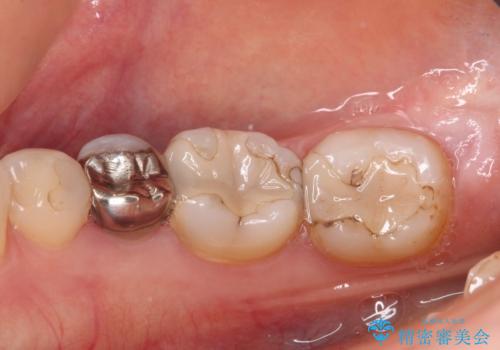

- 奥歯の虫歯を心配して来院した患者様です。

レントゲン写真から、以前治療した詰め物の下に虫歯があることがわかりました。

精度が高く、虫歯の再発リスクの低いゴールドインレーで治療を行うこととしました。